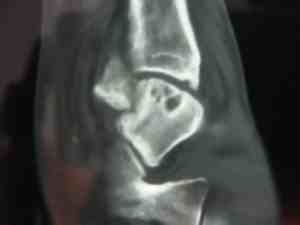

He first consulted me a year and a half later. The ankle was still swollen, and there was considerable discolouration of the skin. Eversion was severely limited.

Fractures in the ankle are notoriously difficult to see because of the overlapping structures. A scan revealed the partially healed fracture through the talus bone.

Worse, because of the disrupted blood supply to the talus, the main bone joining the leg to the foot is dying. A process called "avascular necrosis."

Can you see the great holes of dead bone in the talus? The fracture cut off the blood supply to the osteoblasts. It should have been pinned immediately.

How reliable are X-rays? Sometimes fractures can only be seen on a scan.

Whilst gentle Chiropractic mobilisation of the joints around the talus brought about 50% relief of pain and stiffness for about six months, it's proved temporary. The talus is a major weight-bearing bone. A total ankle replacement is on the cards.

Not because of the original injury, but because the missed fracture led to inappropriate treatment.